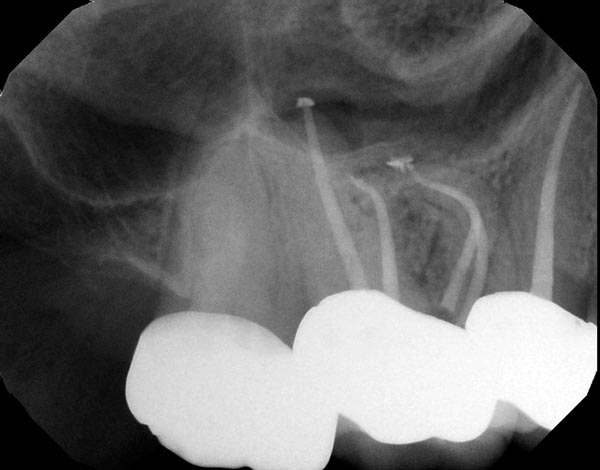

Fig. 3a: Preoperative image of tooth #3 with a necrotic pulp. The MB root illustrates a significant curvature in the apical half of the root, suggesting a highly flexible file as the best alternative. Fig. 3b: The FlexAccess file from Dentsply Sirona was used because of its ability to shape canals efficiently, but mostly because of its extreme flexibility. Fig. 3c: The postoperative image shows the files were able to follow the natural curves of the canal in multiple planes as the MB and ML canals joined in the apical half of the root.

Fig. 3a

Fig. 3b

Fig. 3c